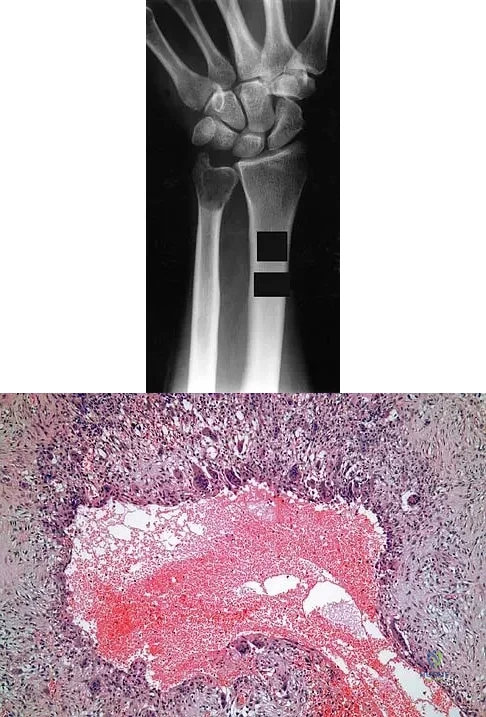

A 30-year-old patient has wrist pain. A radiograph and biopsy specimen are shown in Figures 34a and 34b. What is the most likely diagnosis?

Explanation